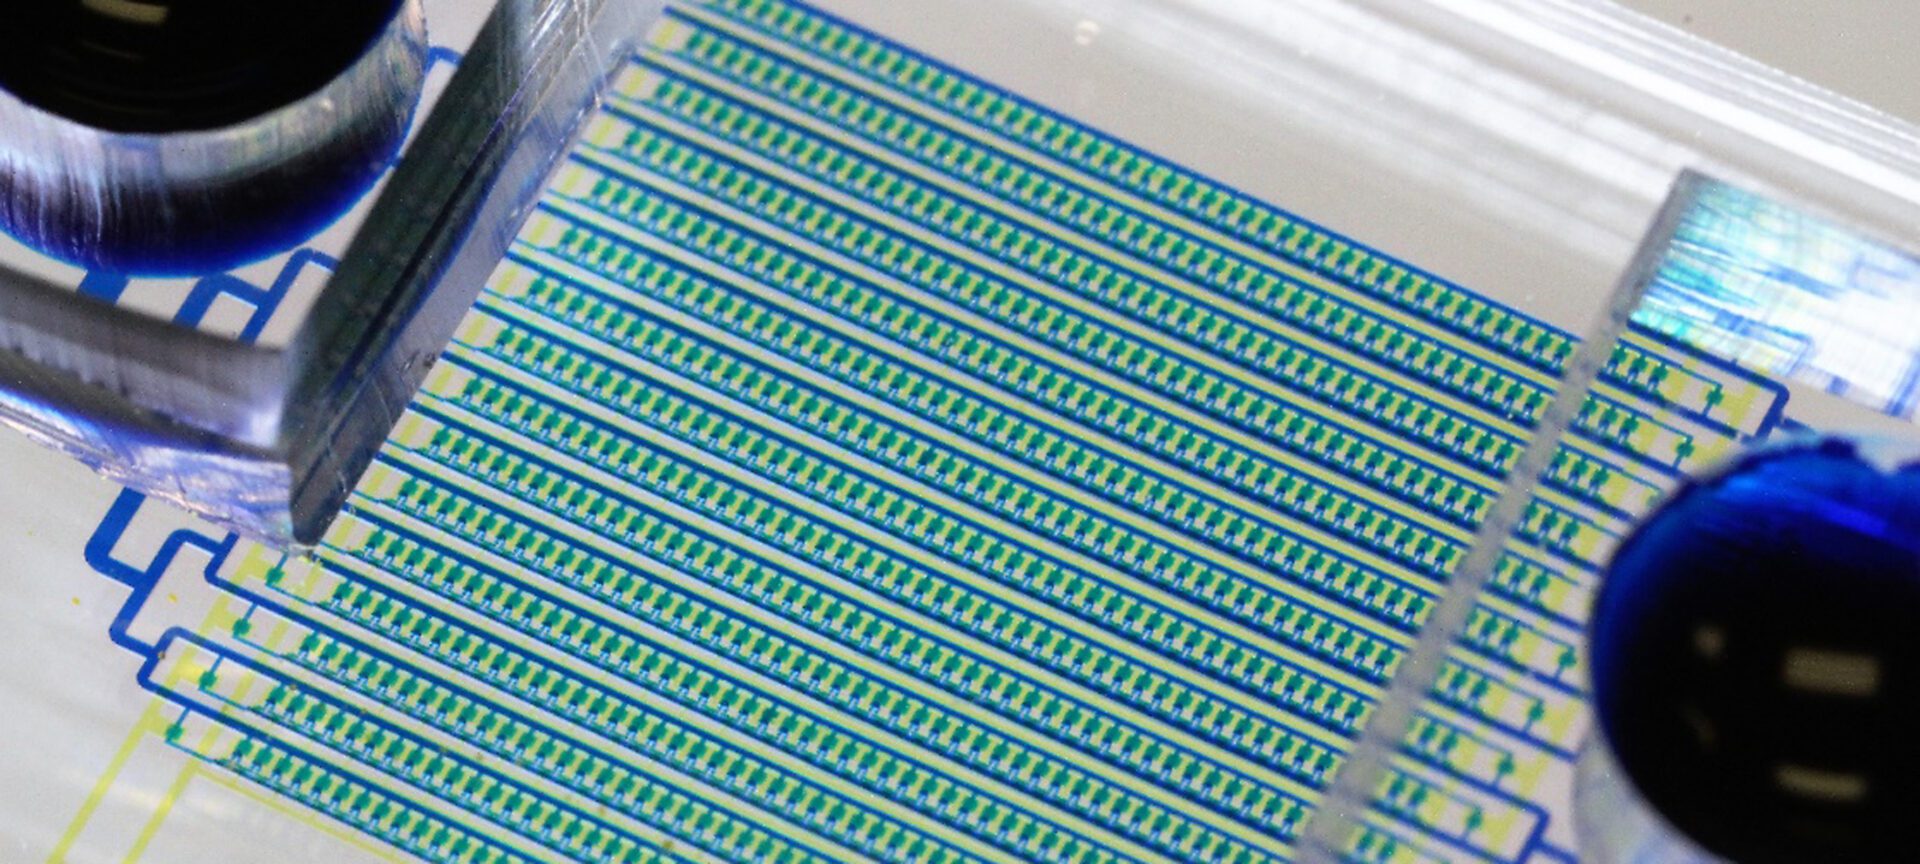

Is lung cancer treatment working? This chip can tell from a blood draw

By trapping and concentrating tiny numbers of cancer cells from blood samples, the device can identify whether a treatment is working at the four-week mark.

Lab-on-a-chip offers faster means of identifying best plasma donors in COVID fight

University of Michigan collaboration with Hackensack Meridian CDI offers new pathway to identify antibodies.